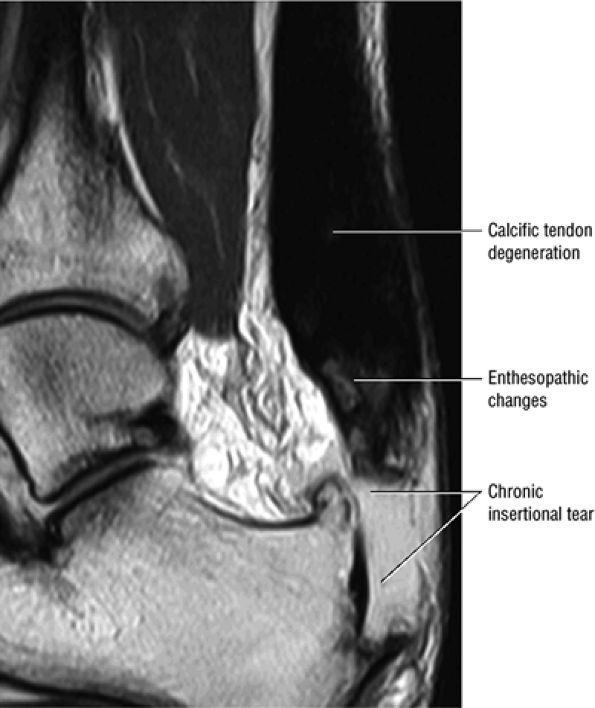

FIGURE 5.113 ● Thickened calcific tendon degeneration in association with distal tendon rupture. Sagittal T1-weighted image.

|

FIGURE 5.114 ● (A) Achilles enthesopathy or insertional tendinitis with dystrophic changes at the enthesis. A plantar enthesophyte is also demonstrated on this sagittal T1-weighted image. (B) A prominent enthesophyte and os calcis insertion tendinosis. Sagittal T1-weighted image.